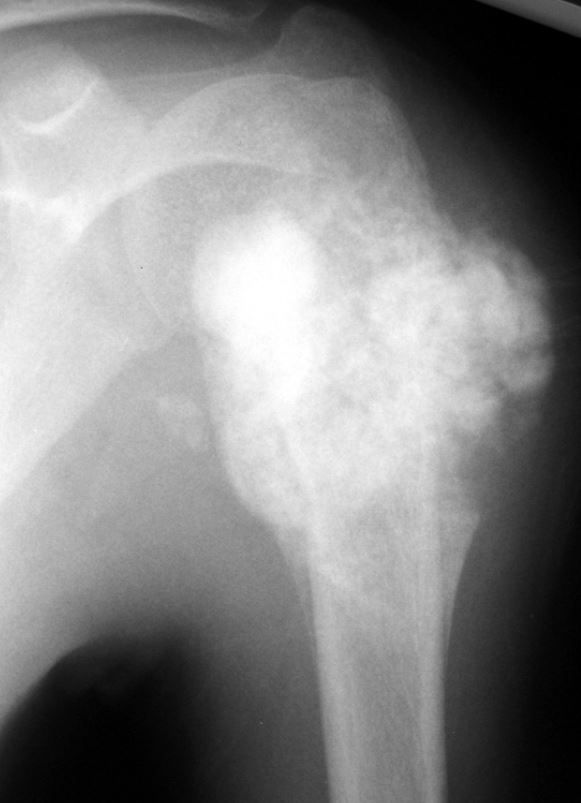

X-ray of osteosarcoma in upper arm bone

An osteosarcoma in the upper humerus (arm bone). The tumors often appear as cloud-like lesions on X-ray.

Reproduced from Weisstein JS, Goldsby RE, O'Donnell RJ: Oncologic approaches to pediatric limb preservation. J Am Acad Orthop Surg 2005; 13:544-554.